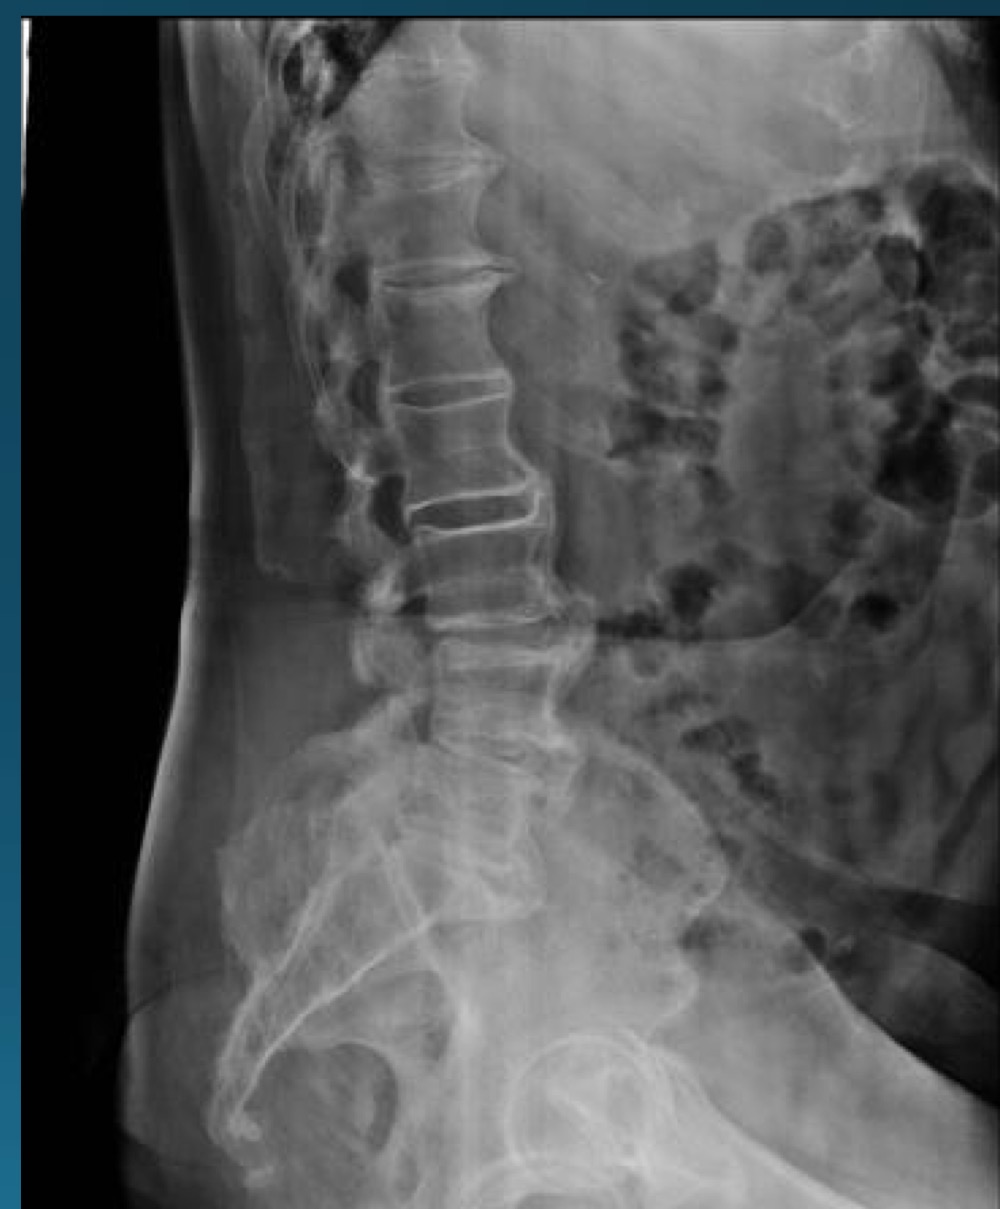

what are the findings in this image?

DISH

what are the 3 diagnostic criteria of DISH?

flowing calcification of at least 4 contiguous vertebral bodies

relative preservation of disc height

abense of facet joint ankylossi and sacroilitis, sclerosis, or intra articular osseous fusion

DISH is the ossification of what ligament

ALL

where is DISH most common?

T7-T11 on right side due to pulsatile descending aorta

what symptoms would you potentially expect with this radiograph?

asymptomatic or stiffness, dysphagia, or joint/tendon pain

what health state has some co-occurence with DISH?

diabetes mellitus

extraspinal DISH might have effects at what sights?

ligamentous and tendionous attachments

is DISH a contraindication to adjusting? if so, what kind?

yes, relative contraindication